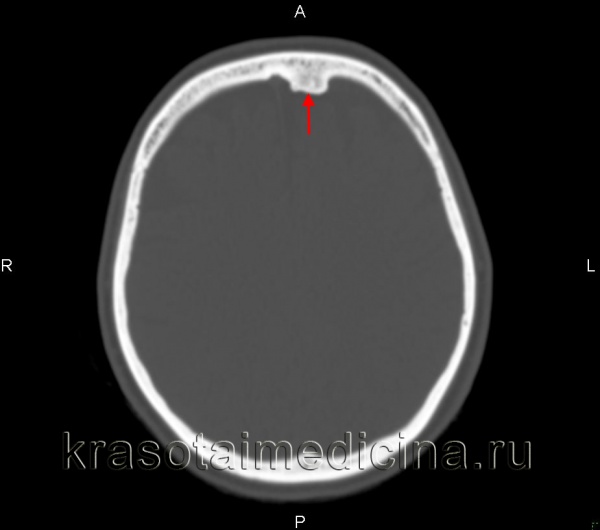

Рентгенограмма остеоид-остеомы проксимального отдела бедра. Имеется рентген-прозрачное образование с четкими контурами, окруженное склерозированной костью. Размеры прозрачного участка всегда меньше 1,5 см. Рентгенограмма голени в прямой проекции: остеоид-остеома малоберцовой кости. Обратите внимание на доброкачественный характер реакции кортикального слоя и увеличение объема кости. Остеоид-остеома диафиза бедра. Обратите внимание на утолщение кортикального слоя кости и доброкачественное периостальное новообразование костной ткани. Еще одним характерным признаком заболевания является интрамедуллярный склероз (стрелка). После рентгенографии методом выбора для диагностики остеоид-остеом является КТ, — очень чувствительный метод обнаружения при интра- и юкстакортикальном расположении «гнезда». Такое поражение сопровождается значительным утолщением кортикального слоя. Обратите внимание на случайное близкое расположение питающей артерии. Очень чувствительным методом диагностики остеоид-остеом является сцинтиграфия костей. В данном случае отмечается значительное усиление сигнала от пораженных дистальных отделов бедренных костей. Аксиальный КТ-срез (а) и взвешенный по Т2 МР-скан (б) с типичными признаками юкстакортикальной остеоид-остеомы дистального отдела бедра. На КТ виден типичный медуллярный склероз вокруг образования. На МРТ—выраженный сопутствующий отек костного мозга и периостальная реакция прилежащей надкостницы. Отечность проксимальной фаланги указательного пальца вследствие остеоид-остеомы. Интраоперационная картина «гнезда». Макропрепарат. «Гнездо» обычно имеет вишневокрасную окраску. При микроскопическом исследовании видны тонкие, хаотично расположенные остеоидные трабекулы, между трабекулами располагается богатая сосудами рыхлая соединительная ткань. При большем увеличении в веществе остеоида видны одинакового вида остеобласты без атипии ядер.

3. КТ при остеоид-остеоме:

• КТ эффективна для диагностики и уточнения локализации опухоли:

о Кортикальное расположение или субпериостальное или интрамедуллярное

• Сопряженная и/или удаленная склеротическая реакция

• Литический очаг ± центральная зона склероза

• К очагу часто примыкают питающие сосуды

• КТ контроль при чрескожной радиочастотной абляции

о КТ подтверждает наличие опухоли и уточняет место ее расположения